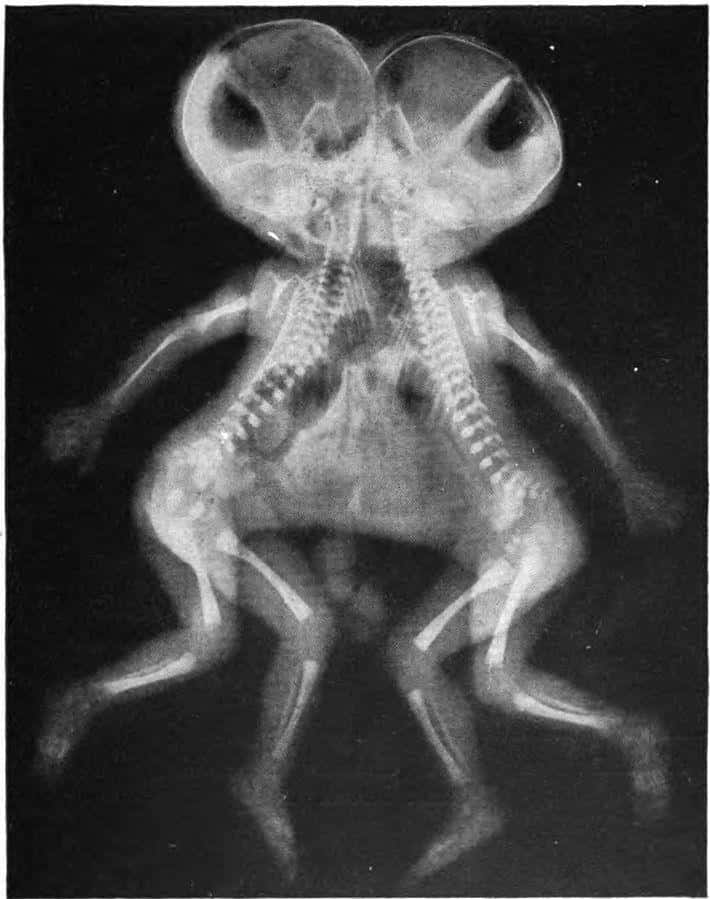

Existuje mnoho rôznych typov siamských dvojčiat

Existuje viac ako tucet klasifikácií pre siamské dvojčatá podľa toho, na akom mieste sú súrodenci spojení. Jednou z najbežnejších foriem siamských dvojčiat sú thoracopagus dvojčatá. Ide o dvojčatá spojené v hornej časti hrudníka a zdieľajú srdce. V tomto prípade nie je možné ich telá oddeliť bez toho, aby sa doktor opýtal pacienta. Ďalším bežným typom spojených dvojčiat je omfalopagus. Tieto dvojčatá sú spojené od stredu hrudníka k oblasti pupka, ale nemajú spoločné srdce. Často majú spoločnú pečeň a dokonca aj pohlavné orgány.

Spoločne tvoria thoracopagus a omfalopagus dvojčatá asi 75% všetkých siamských dvojčiat .

Kraniopágové dvojčatá, spojené na lebke, predstavujú jeden z najvzácnejších typov spojených dvojčiat.